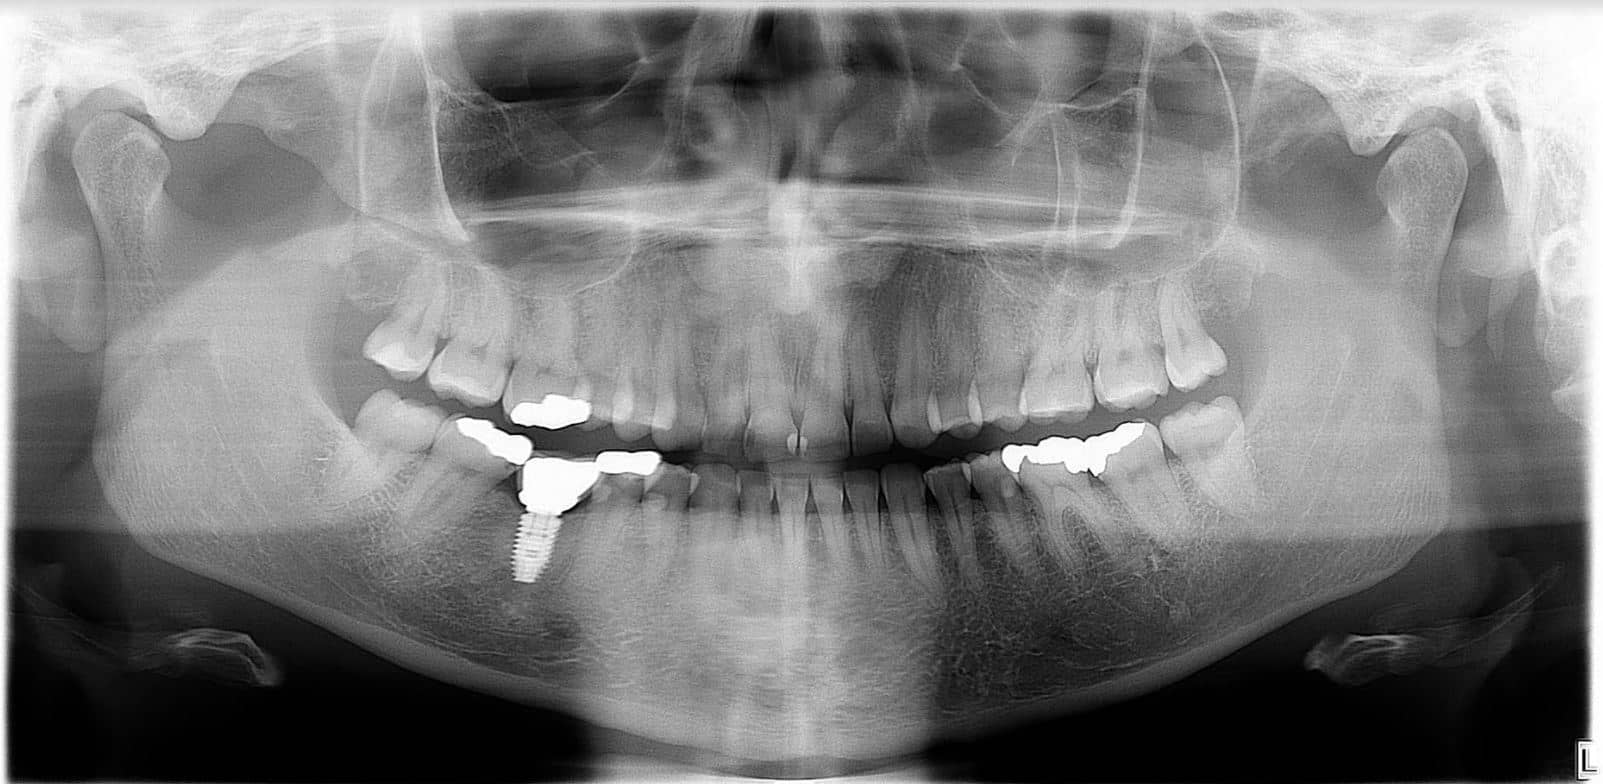

A másik kategóriát az extraorális röntgenvizsgálatok képezik. Az extraorális röntgenek esetén mind a sugárforrás, mind a film/digitális érzékelő a szájon kívül helyezkedik el. Ebben az esetben nagyobb területről, általában az egész szájüregről készítünk képet. Ide tartozik a panorámaröntgen is. Íme, egy panorámaröntgennel készített kép: